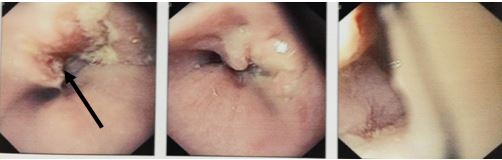

Bệnh nhân được chỉ định chụp PET/CT để đánh giá tình trạng u, hạch, di căn xa

- Kết quả chụp PET/CT vào tháng 6/2013:

- Tổn thương tăng hấp thu FDG mạnh đoạn thực quản 1/3 giữa, max SUV 10,72, kích thước 3x4,6x6,7 (cm)

- Tổn thương vùng xoang lê bên phải tăng hấp thu FDG mạnh, max SUV 9,47, kích thước 1,5x2x2,5cm

- Không thấy hạch trung thất, hạch cổ hai bên

- Các cơ quan bộ phận khác không thấy tăng hấp thu FDG bất thường

Hình 3. Hình ảnh PET/CT: Khối u thực quản 1/3 giữa - dưới (màu đỏ), khối u vùng hạ họng (xoang lê) phải (màu vàng.